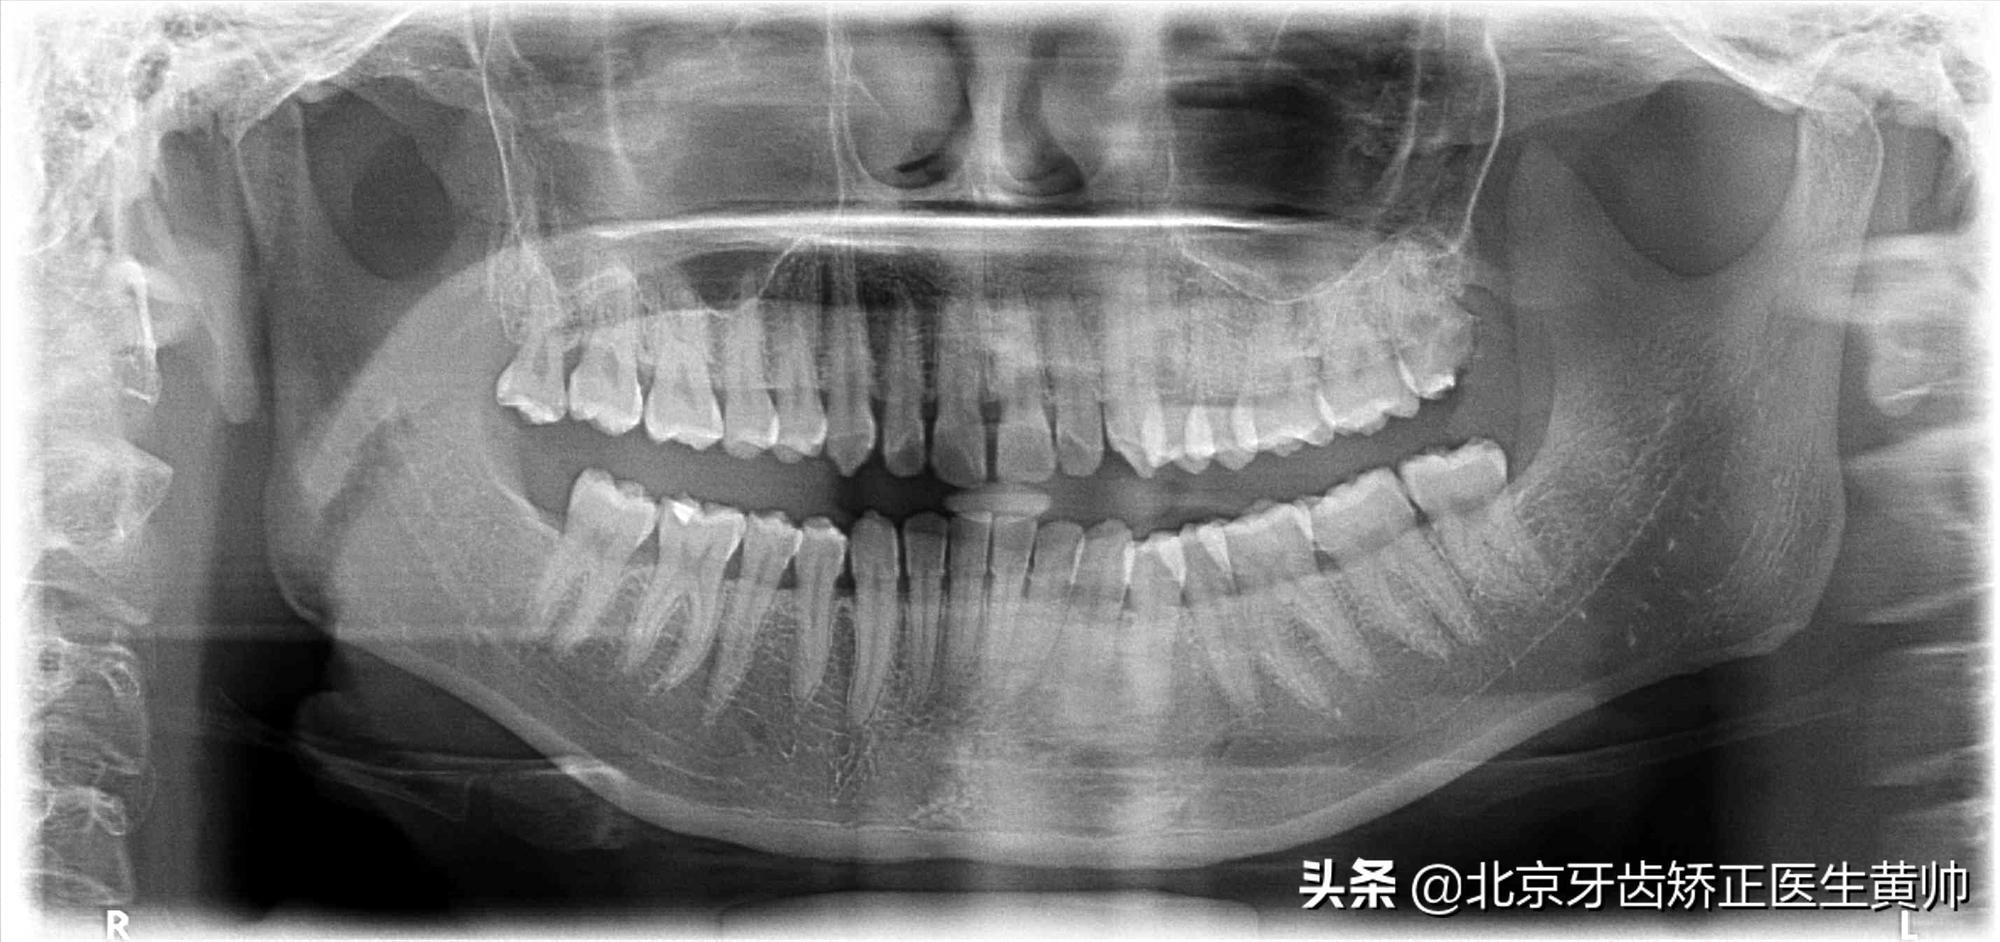

在孩子进行牙齿矫正之前,有必要做一下相关的检查,包括面部以及牙颌照片、拍摄头颅侧位片和全口曲面断层片等。

曲断全景片